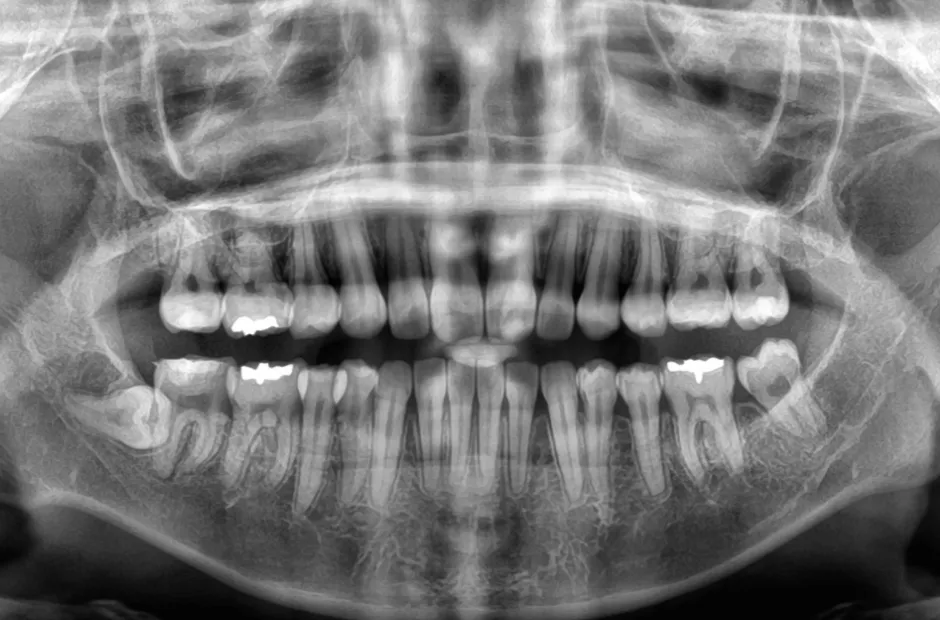

叢生

| 診断名・主訴 | 叢生 |

|---|---|

| 年齢・性別 | 43歳・女性 |

| 治療期間・回数 | 2年7か月 27回 |

| 治療に用いた主な装置 | 舌側矯正 |

| 抜歯部位 | 両顎4,4 |

| 治療費 | 100万円(税抜) |

| リスク・副作用 | 装置による違和感・疼痛・歯肉退縮・歯根吸収・虫歯のリスクなど |

治療後